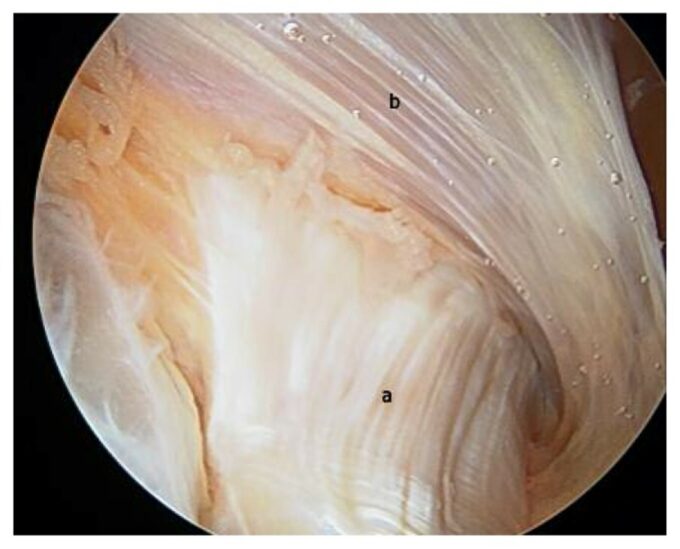

Replacement of the normal long-chained HA by short-chained HA triggers fascial tension, adhesions, and fascial scarification. These pathological changes dramatically affect the health and performance of underlying skeletal muscles. Figures 3 and 4 illustrate endoscopic pictures taken during surgery of healthy and damaged fascia.

Fig. 3. Endoscopic picture of healthy fascia (Carro et al, 2016)

Fig. 3 presents a live endoscopic picture of the healthy deep fascia, which covers vastus lateralis part of the quadriceps muscle (‘b’ indication in the picture) at its origin at the periosteum of the upper femur. The powerful, thick tendon (‘a’ indication in the picture) seen at the bottom of the picture is the tendinous part of the gluteus maximus muscle at its insertion into the periosteum of the femur. Notice the smooth, pearl-colored appearance of the healthy, deep fascia and many droplets of HA-based lubrication.